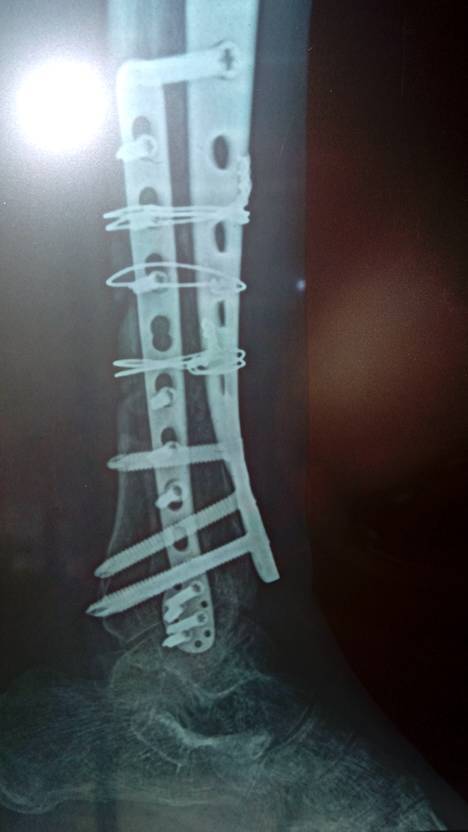

粉碎型小腿胫骨骨折后植骨排骨骨折至今以有八个月还没有骨痂生长请问有什么办法叫骨生长快谢谢了 点击展开 匿名用户 2014-06-06 17:11 为您推荐: 其他回答 部分负重,就是把一部分体重给伤肢负重,骨折在应力作用容易生长。加强营养,补充钙剂,维生素D.还可以吃骨肽促进骨质生长。 xyzktc 2014-06-07 21:01 相关问题 我小腿胫骨粉碎骨折后植骨排骨骨折以有八个月了去拍片医生说就没有骨痂生长需要在植骨有什么办法叫骨痂生 小腿胫排骨粉碎性骨折用外固定架五个月了骨头基本模糊还得多长时间能踩地活动 小腿胫排骨断裂性骨折 取出刚板五个月了 可受伤的这个腿还是不那么灵活 想问